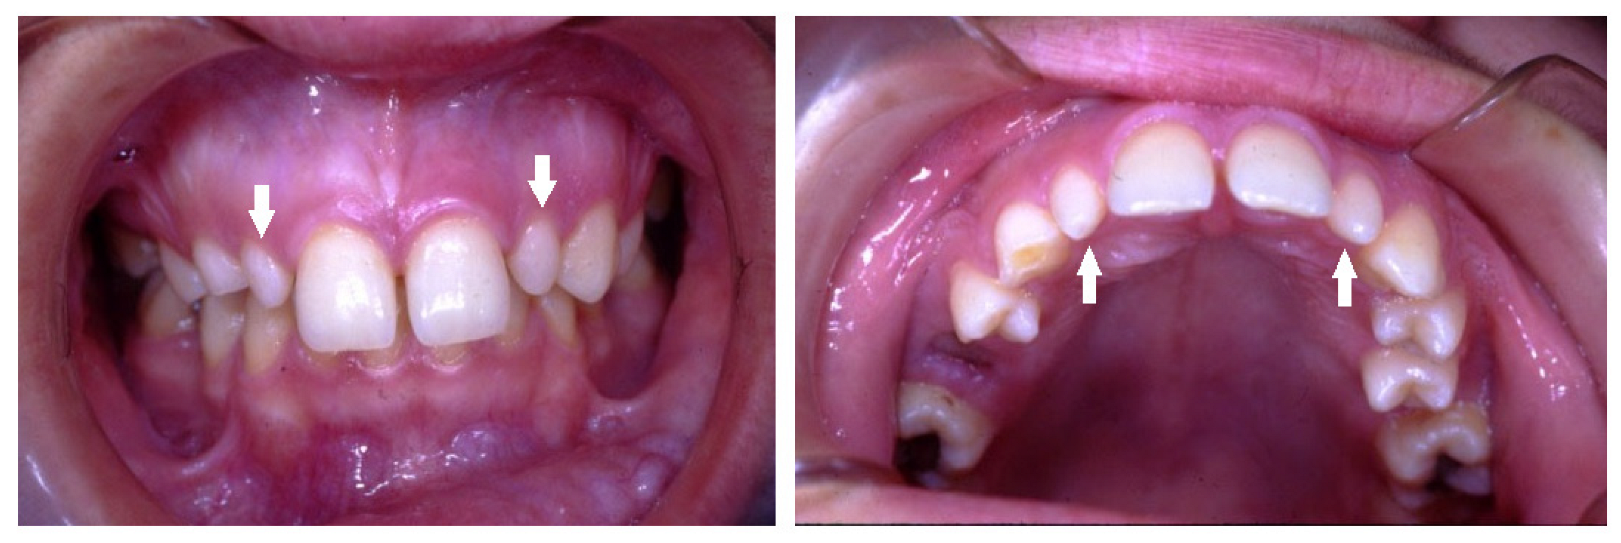

| Peg-shaped | Small conical tooth with a narrowing in diameter from the cervix to the in-cisal edge. |

| Ectopic | Eruption of teeth not in their normal position. |

| Submergence | A primary tooth positioned under the occlusal surface of the adjacent teeth. |